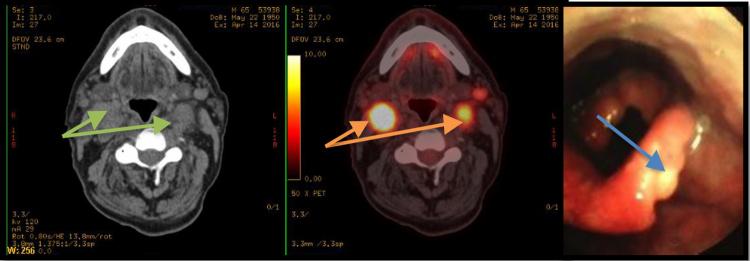

https://cdn.ncbi.nlm.nih.gov/pmc/blobs/5742/7063163/46669c2072e4/gr1.jpg